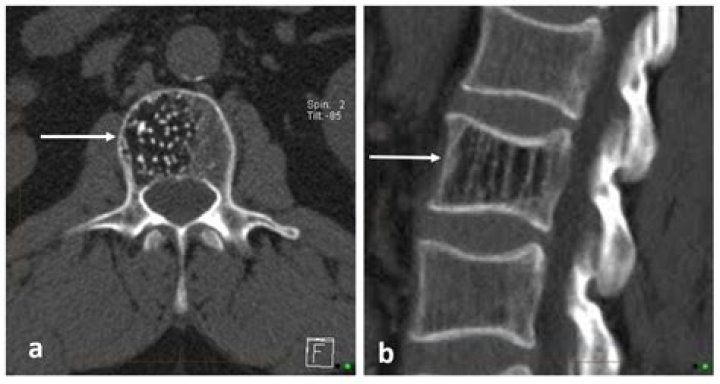

Can CT scan detect spinal tumor?